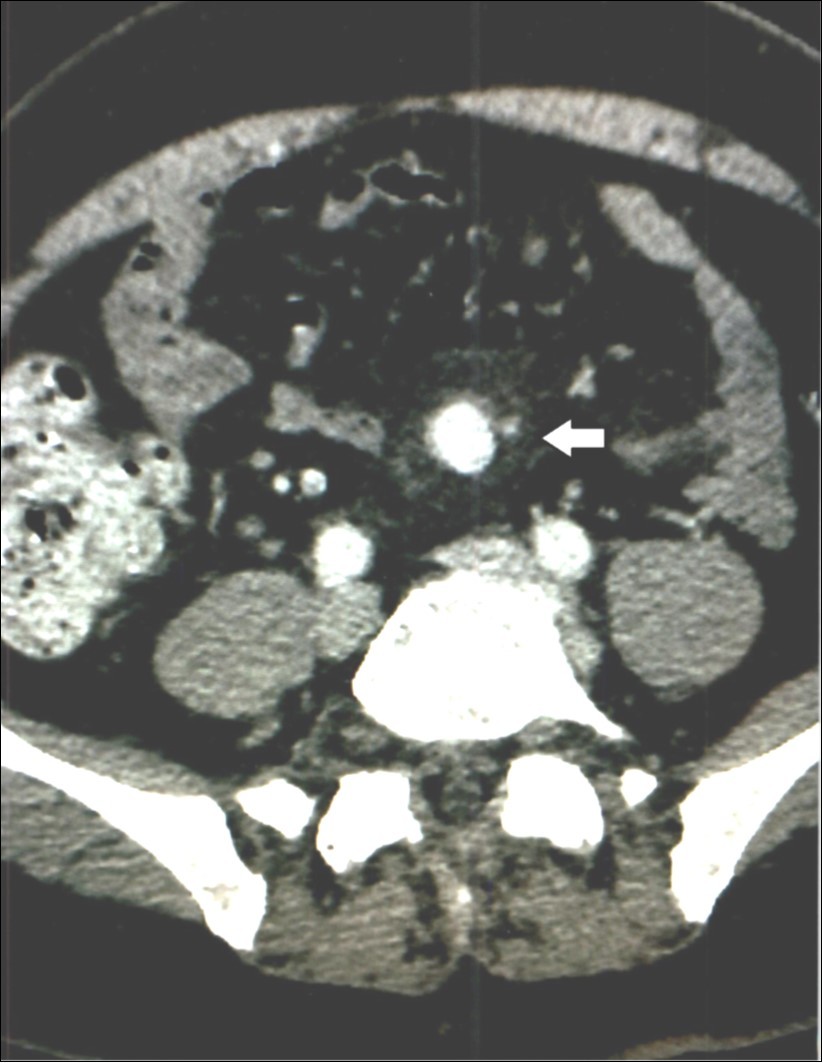

Complete metabolic panel was normal with normal hemogram. Immediate computed tomography (CT scan) revealed a 1.5 x 2 centimeter mesenteric aneurysm, possibly ruptured, Figure 2, as well as two smaller aneurysms a few millimeters each in diameter and abdominal aortic and carotid dilatation. A few small galls stones were seen. Immediate percutaneous embolization of the large aneurysm was performed two days before the procedure and six days afterward he received Levaquin. Follow up CT scan of the abdomen 18 months later showed the embolized mesenteric aneurysm and no change in the smaller ones. The symptoms have not recurred two years later.

Figure 2.Case 2 – Superior Mesenteric Artery Branch Aneurysm.

In our second patient, Case 2, in addition to the aneurysm, the CT scan indicated “probable” bleeding, Figure 2, without any sign of systemic bleeding or infection, clinically or in the hemogram. The blood cultures were normal six days after treatment. White blood cell counts were normal and only mild anemia was present. Therefore, it is doubtful the aneurysm was mycotic. The “halo” around the aneurysm can be interpreted as pressure effect of the enlarging aneurysm on the surrounding tissues.